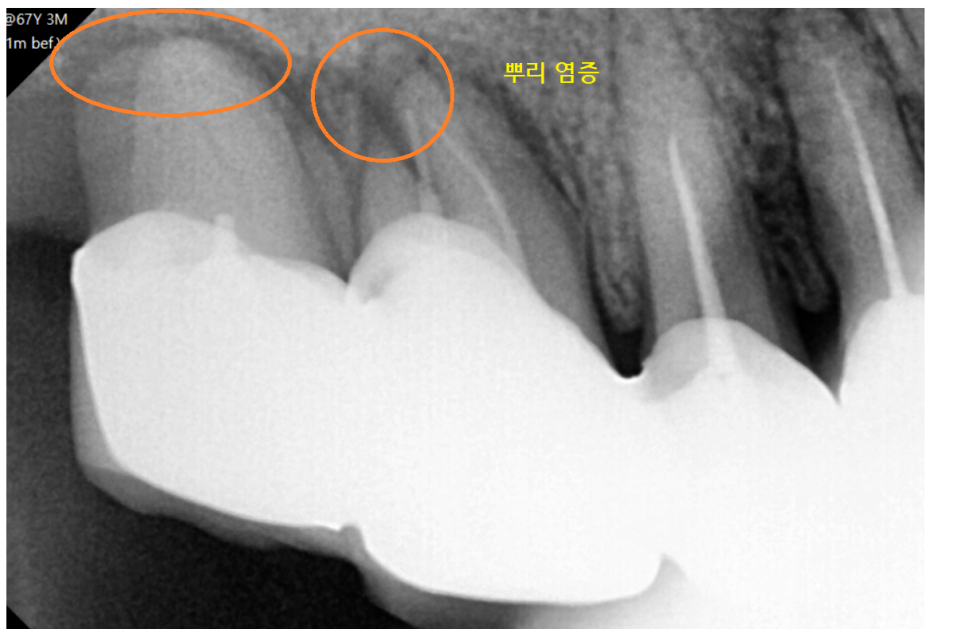

주변 잇몸뼈가 이미 다 녹아있어

그대로 둬도 좋을게 없었습니다.

옆에 치아 잇몸뼈까지 녹일 수 있는 상황이었거든요.

명일동 치과에서 발치 후 임플란트를 하시기로

설명드렸습니다.

23.06.07

뿌리 염증이 오래된 경우

만성화되면 염증이 있어도 아프지 않은데요.

오늘 환자분처럼 주변 잇몸뼈를 녹여

뼈 이식까지 진행할 수 있기에

문제가 생겼을 때 바로 치료받으시는 게 좋습니다.